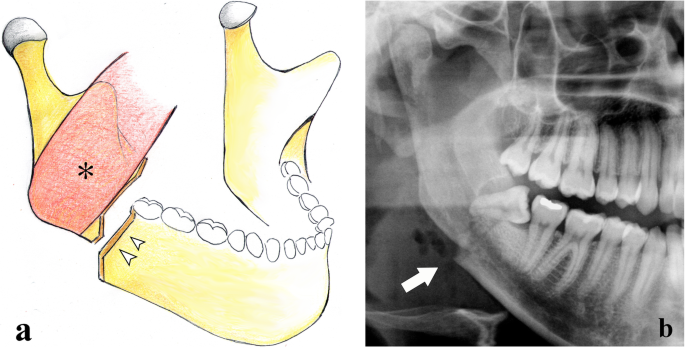

Fractures of the horizontal branch are located in the area between the canine and mandibular angle. These fractures can be qualified as unfavourable or favourable on the basis of the direction of the fracture rhyme and the muscle attachment points that lead to displacement or no displacement of bone fragments, respectively (Fig. 4). The masseter, temporal, and medial pterygoid muscles pull the horizontal branch upwards, whereas the digastric, geniohyoid, and mylohyoid muscles move the mandibular symphysis downwards. Therefore, the fracture is unfavourable when the fracture rhyme runs from the alveolar ridge to the lower mandibular cortex with a posterior direction since the bone fragments are displaced. On the contrary, the fracture is favourable when the fracture rhyme runs anteriorly since the bone fragments are moved towards each other with no displacement [22].

Horizontal branch fractures. a Unfavourable fracture. Picture showing a fracture with a downward and posterior direction. The bone fragments are misaligned by the action of the masseter muscle (black arrow) that pulls the distal bone fragment upwards, and the mylohyoid (asterisk), geniohyoid (white arrow), and anterior belly of digastric (black arrowhead) muscles that pull the mesial bone fragment downwards. b Favourable fracture. Picture showing a fracture with a downward and anterior direction. The bone fragments impact each other with no displacement. c, d Cropped panoramic radiographs in toothless patients with unfavourable (arrow) and favourable (arrowhead) horizontal branch fractures